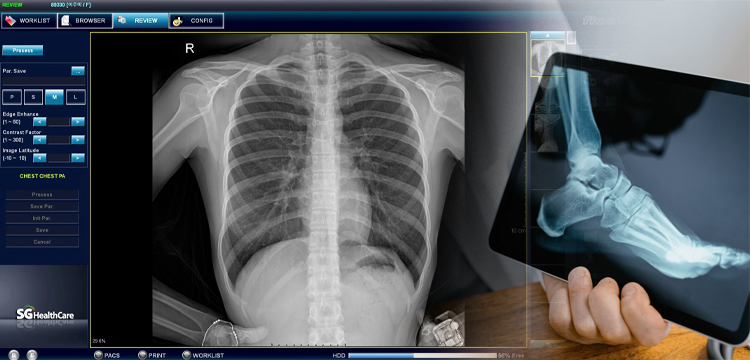

Contamos con equipos de rayos x digitalizados para la realización de cualquier estudio Radiologico como son:

• Estudios contrastados con nuestro gabinete asociado

• Radiografía de Cabeza y Cuello

• Radiografía de Tórax

• Radiografía de Abdomen

• Radiografía de Pelvis

• Radiografía de Extremidades superiores

• Radiografía de Extremidades inferiores

Images